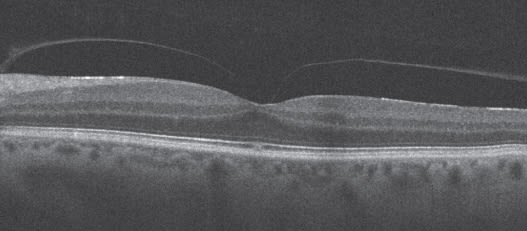

Vitreomacular traction syndrome can be difficult even for a retina specialist to diagnose without SD-OCT. Let's say a patient has reduced vision and a moderate cataract, but the vision seems to be just a little bit worse than the cataract surgeon would expect it to be. There is no macular degeneration, no macular hole and no macular pucker. There might be a subtle reddish-yellowish change in the fovea. You scratch your head and say what's going on with this patient? With Cirrus HD-OCT, it is obviously vitreomacular traction syndrome (Figure 2). You may also have a patient who appears to have dry macular degeneration, but if SD-OCT shows fluid and the patient is not diabetic, almost always the patient has an occult choroidal neovascular membrane that needs to be addressed before the cataract is removed.

Figure 2. Vitreomacular traction syndrome can be especially difficult to diagnose without SD-OCT.